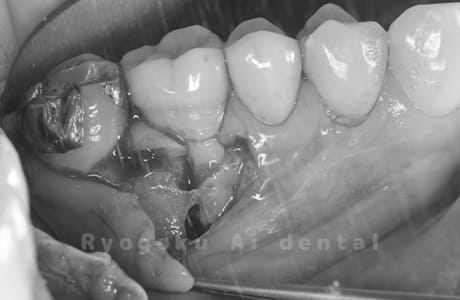

他院で根管治療を行ったが、なかなか治らず、抜歯を宣告されたとのことでご来院された患者様です。歯がかなり削られており、また、歯根の根尖部の病変が大きく、嚢胞化しているため、クラウンレングスニングと再植歯根端手術を同時に行いました。違和感もなくなり、大変満足されています。

<リスク・副作用>

外科手術のため、術後に出血、痛みや腫れ、違和感を伴います。口腔内の状態によっては適応できないことがあります。歯根端切除で治らなければ抜歯を検討しなくていけない場合もあります。